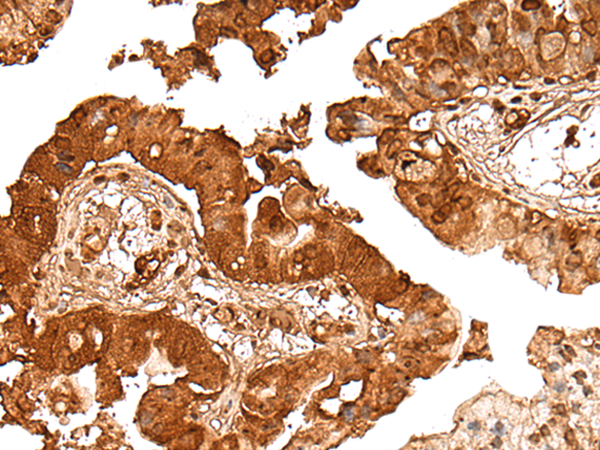

(The image on the left is immunohistochemistry of paraffin-embedded Human esophagus cancer tissue using DEDD2 Antibody at dilution 1/30, on the right is treated with fusion protein. (Original magnification: x200))

(The image on the left is immunohistochemistry of paraffin-embedded Human colorectal cancer tissue using DEDD2 Antibody at dilution 1/30, on the right is treated with fusion protein. (Original magnification: x200))